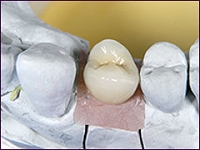

・天然歯と見分けのつかない審美性

インプラントは、埋め入れる位置や角度、噛み合わせ、周りの歯との調和を考えられて埋入されるので、違和感がない見た目となります。

被せ物も、透明感と自然なツヤのセラミック素材を使用することが多いので、天然の歯のような審美性を手に入れることができます。